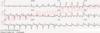

Du bliver kaldt til KARMA, hvor en 64-årig mand netop blev indlagt med hjertebanken gennem de sidste 3 dage. På indlæggelsesdagen har han desuden fået lidt åndenød ved fysisk aktivitet. Der er ingen brystsmerter. Patienten er kendt med PCI og stentning af en stenose midt på LAD for 5 måneder siden på grund af non-ST-elevationsmyokardieinfarkt (NSTEMI) og blev i denne sammenhæng sat i antitrombotisk behandling med Magnyl 75 mg x 1 og ticagrelor 90 mg x 2. Patienten er desuden kendt med hypertension gennem ca. 10 år og hyperkolesterolæmi, som har været velbehandlet. Herudover har patienten ikke fejlet noget. Blodtrykket ved ankomsten til KARMA 145/95. EKG viser atrieflimren med ventrikelfrekvens omkring 120/min. Ekkokardiografi viser normal systolisk funktion af venstre ventrikel. Standardblodprøverne er normale (inkl. væsketal). Du påbegynder frekvensregulerende behandling med metoprolol og beslutter, at patienten skal DC-konverteres. Patienten har en CHA2DS2- VASc score på 2.